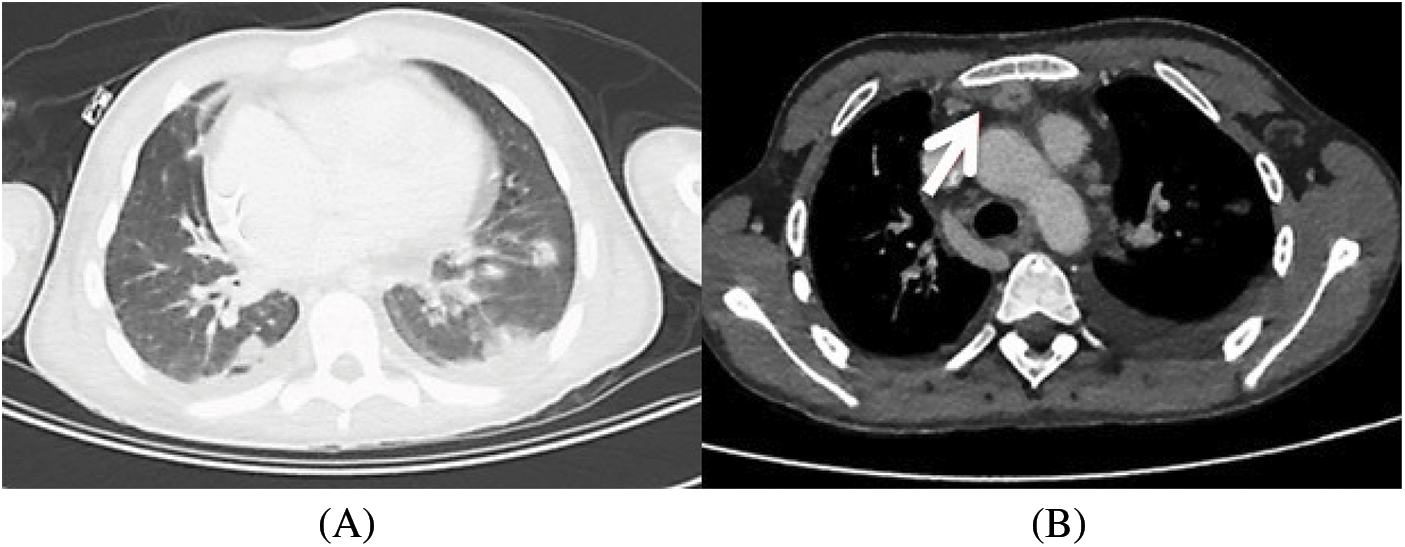

The diagnosis of endocarditis was confirmed by a PET-SCAN with suspicion of an abscess between the upper part of the conduit and the sternum. In addition, it revealed secondary septic localizations with multiple pulmonary lesions suggestive of pulmonary emboli, as well as a right hip arthritis (Fig. 1).

Figure 1: CT scan that shows pulmonary embolism (1A) and mediastinal collection (1B)